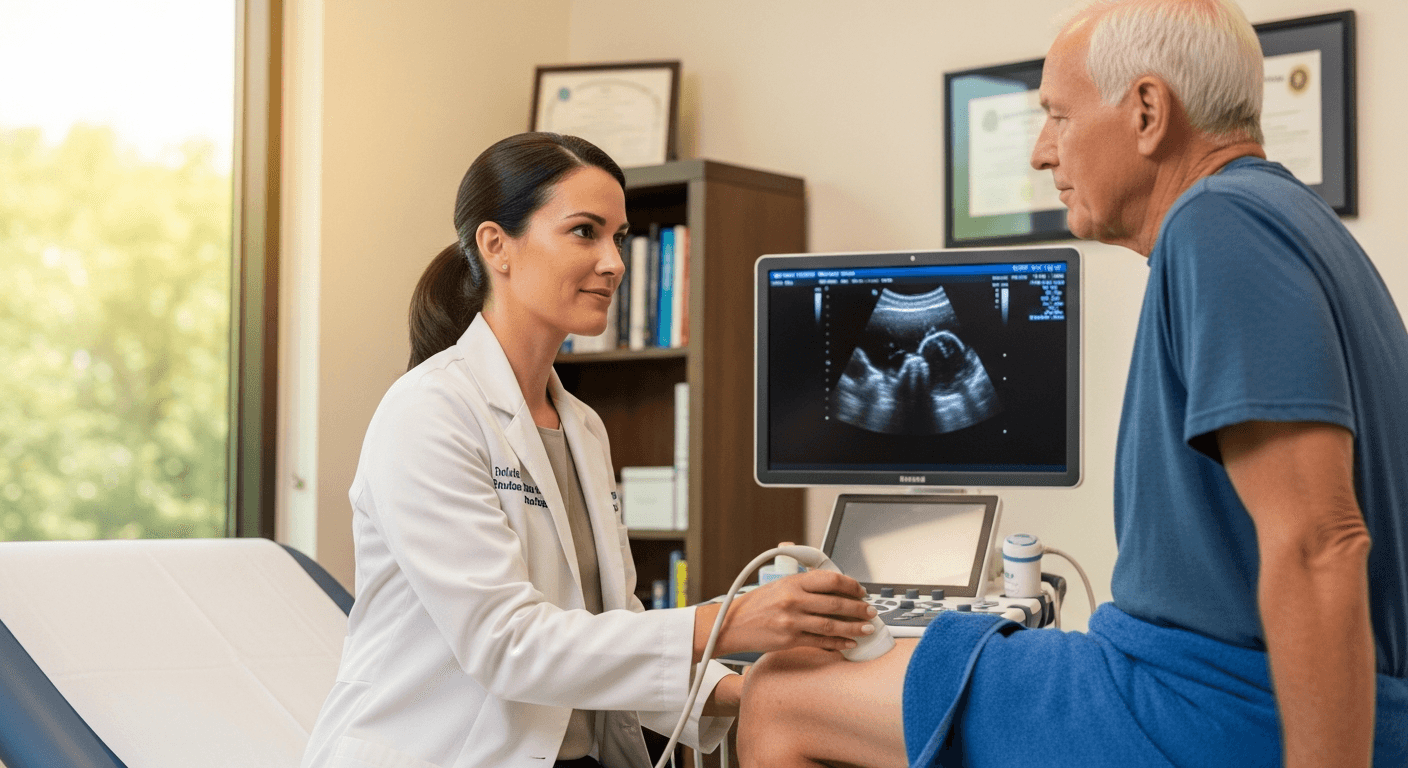

When you come to M&S for knee or shoulder pain, you meet a board-certified specialist who reviews your own imaging with you, explains what is causing the pain, and walks through every option. We look at minimally invasive, non-surgical approaches whenever they fit your case, so you understand the plan before anything moves forward.

Minimally Invasive Procedure

Image-guided, catheter-based treatment in our outpatient suite. No general anesthesia, no incision — conscious sedation only.